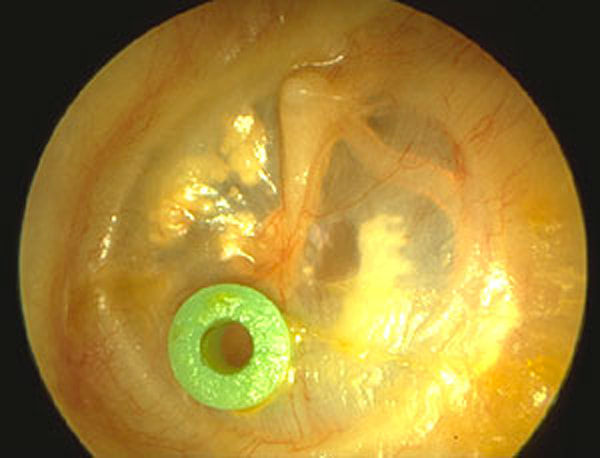

Le drain transtympanique est un petit tube inséré dans le tympan afin d’assurer l’aération de l’oreille moyenne et d’éviter l’accumulation de liquide. Il est principalement utilisé en ORL chez l’enfant et parfois chez l’adulte pour traiter les otites séreuses chroniques.

Le drain transtympanique, aussi appelé yoyo, est un micro-tube placé dans le tympan après une petite incision.